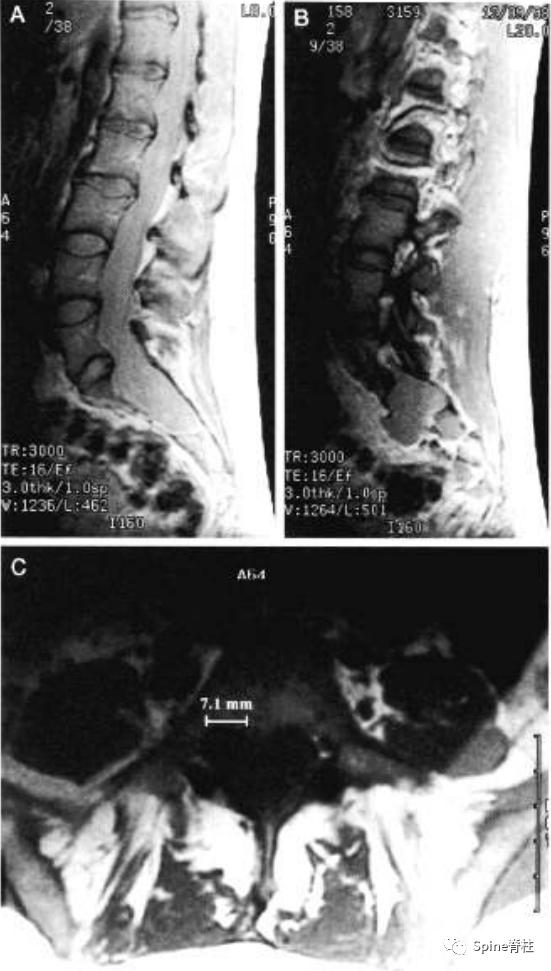

一个马凡综合征伴硬膜扩张患者的MRI。a为T2正中矢状位提示S2硬膜囊的宽度大于L4,存在骶骨前硬膜膨出,S1的扇形缺损值为5.1。c为横断面提示一个神经根袖直径>7.0mm。因此,这个患者满足两个主要标准和两个次要标准。